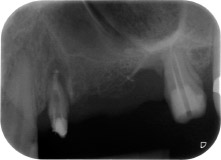

apikale Parodontalläsion an Zahn 24

Abb. 1: Bei einer 58-jährigen Patientin zeigt die Röntgenaufnahme vor der OP eine apikale Parodontalläsion an Zahn 24 und einen horizontalen Knochenabbau im zweiten Quadranten.

Eine 58-jährige Patientin, die auch eine gute Freundin und ärztliche Kollegin ist, beschwerte sich über Schmerzen und erhöhte Beweglichkeit ihres Brückenpfeilers 24. Es lag auch eine parodontale Entzündung vor, mit Taschentiefen von 7 mm mesiobukkal und mehr als 12 mm distal und einer Furkationsbeteiligung dritten Grades. Darüber hinaus zeigte die Röntgenaufnahme eine großflächige apikale Aufhellung am endodontisch (alio loco) vorbehandelten Zahn 24 (Abb. 1).

Ein Jahr zuvor waren die Zähne 25 und 26 vor dem Einsetzen der Brücke aufgrund traumatischer und endoparodontaler Ursachen extrahiert worden. Eine Paro-Endo-Läsion wurde bei unklarer ätiologischer Hauptkomponente für den Zahn 24 diagnostiziert. Die Patientin machte deutlich, dass sie ihre Pfeilerzähne 24 und 27 behalten und keinen endgültigen oder temporären herausnehmbaren Zahnersatz akzeptieren will. Darum wurde vereinbart, alles zu versuchen, beide Zähne, trotz der nach den radiologischen und klinischen Befunden als schlecht einzustufenden Prognose, zu erhalten.

An der bukkalen Wurzel fehlte der gesamte vestibuläre und distale Knochen. Das Attachment beschränkte sich weitgehend auf die palatinale Wurzel, was die anfängliche schlechte Prognose unterstreicht. Auch Zahn 27 wies ein verringertes horizontales Attachment (vgl. Abb. 12) und eine kleine apikale Aufhellung (Abb. 1) auf, allerdings ohne klinische Symptome.